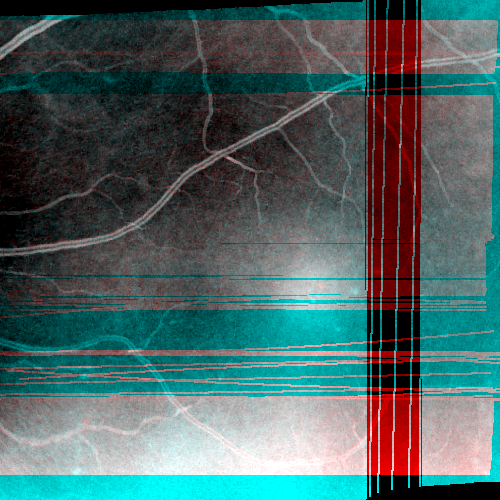

Images and estimated displacements are shown for a representative scan in Figureย 3. Tiny discontinuities prove absence of overregularization, and consistent transverse vibration indicates partial correction of ocular tremor. For quantitative analysis, we computed the median distance between the aligned A-scan displacements, and the fraction of displacements with a distance above 0.5 (problematic for supersampling) and 1 pixels (misalignments). The first and last 5% of B-scans were excluded, because they might not overlap with the orthogonal data, preventing registration. As the distributions are heavily skewed, we present box plots in Figureย 4. The three outliers in each direction in the right plot originate from the same subject, which is shown in supplementary Figureย 6. It is critical to note that the parameter density (B-scan rate 205 Hz) of the hermite splines is insufficient to fully correct ocular tremor (frequency up to 100 Hzย [16]). Therefore, this aperiodic, wave-like motion (amplitude 30โฒโฒ 1.6ย ยตm on the retinaย [16]) cannot be fully corrected, and neither is fully represented in the reproducibility error. In the transverse directions, this puts a lower accuracy limit on the evaluation scheme, but it is small compared to the pixel spacing (12ย ยตm). Using an Nvidia RTX 5000 GPU, the median and maximum runtime in the test set, excluding disk I/O which is irrelevant in clinical routine, was 8.6ย s and 31.3ย s. Tableย 1 compares average runtimes of various methods. Lastly, registration of individual B-scan repeats is demonstrated on a swept-source scanner in Figureย 5.